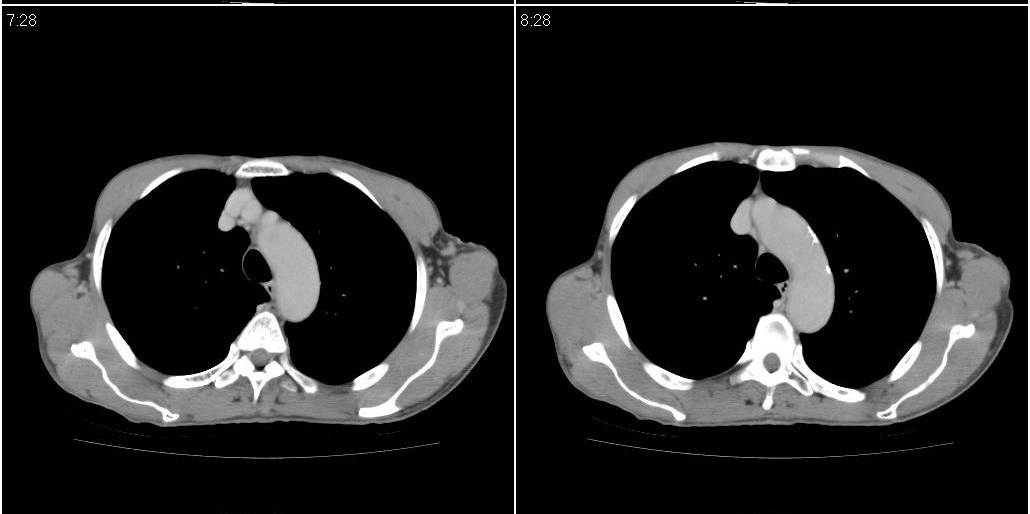

标题: CT25416:男性,70岁。胸片发现右下肺斑片状阴影 [打印本页]

标题: CT25416:男性,70岁。胸片发现右下肺斑片状阴影

以下是ct检查的情况:

考虑右肺下叶炎症可能性大?未除占位,建议增强。右下肺肺不张

右下胸壁皮下气肿。

右下肺阻塞性肺炎!建议纤支镜!

右肺中叶阻塞性不张及肺炎,高度怀疑支气管占位,建议纤支镜检查!